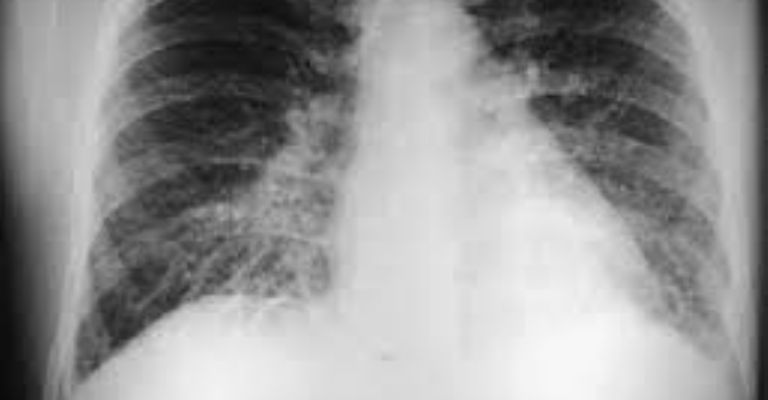

Sin embargo, el virus puede ser más agresivo y causar el denominado síndrome pulmonar por hantavirus que podría tener consecuencias mortales.

Esta complicación médica, según datos de la Organización Mundial para la Salud, tiene una tasa de mortalidad de 38% y no existe tratamiento específico.